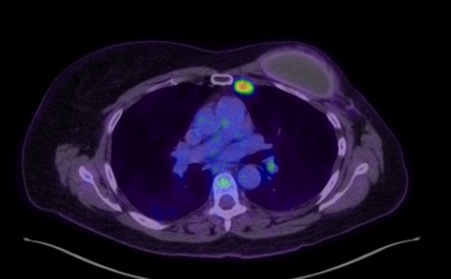

A PET CT scan following the FNA showed intense fluorodeoxyglucose (FDG) uptake in two enlarged left internal mammary lymph nodes at the second and third intercostal space with standardised uptake value (SUV) max of 7.35 (Figure 3). Low grade FDG uptake, likely reactive or inflammatory, was seen in the left axilla and bilateral cervical nodes. There was no significant uptake surrounding left breast prosthesis.